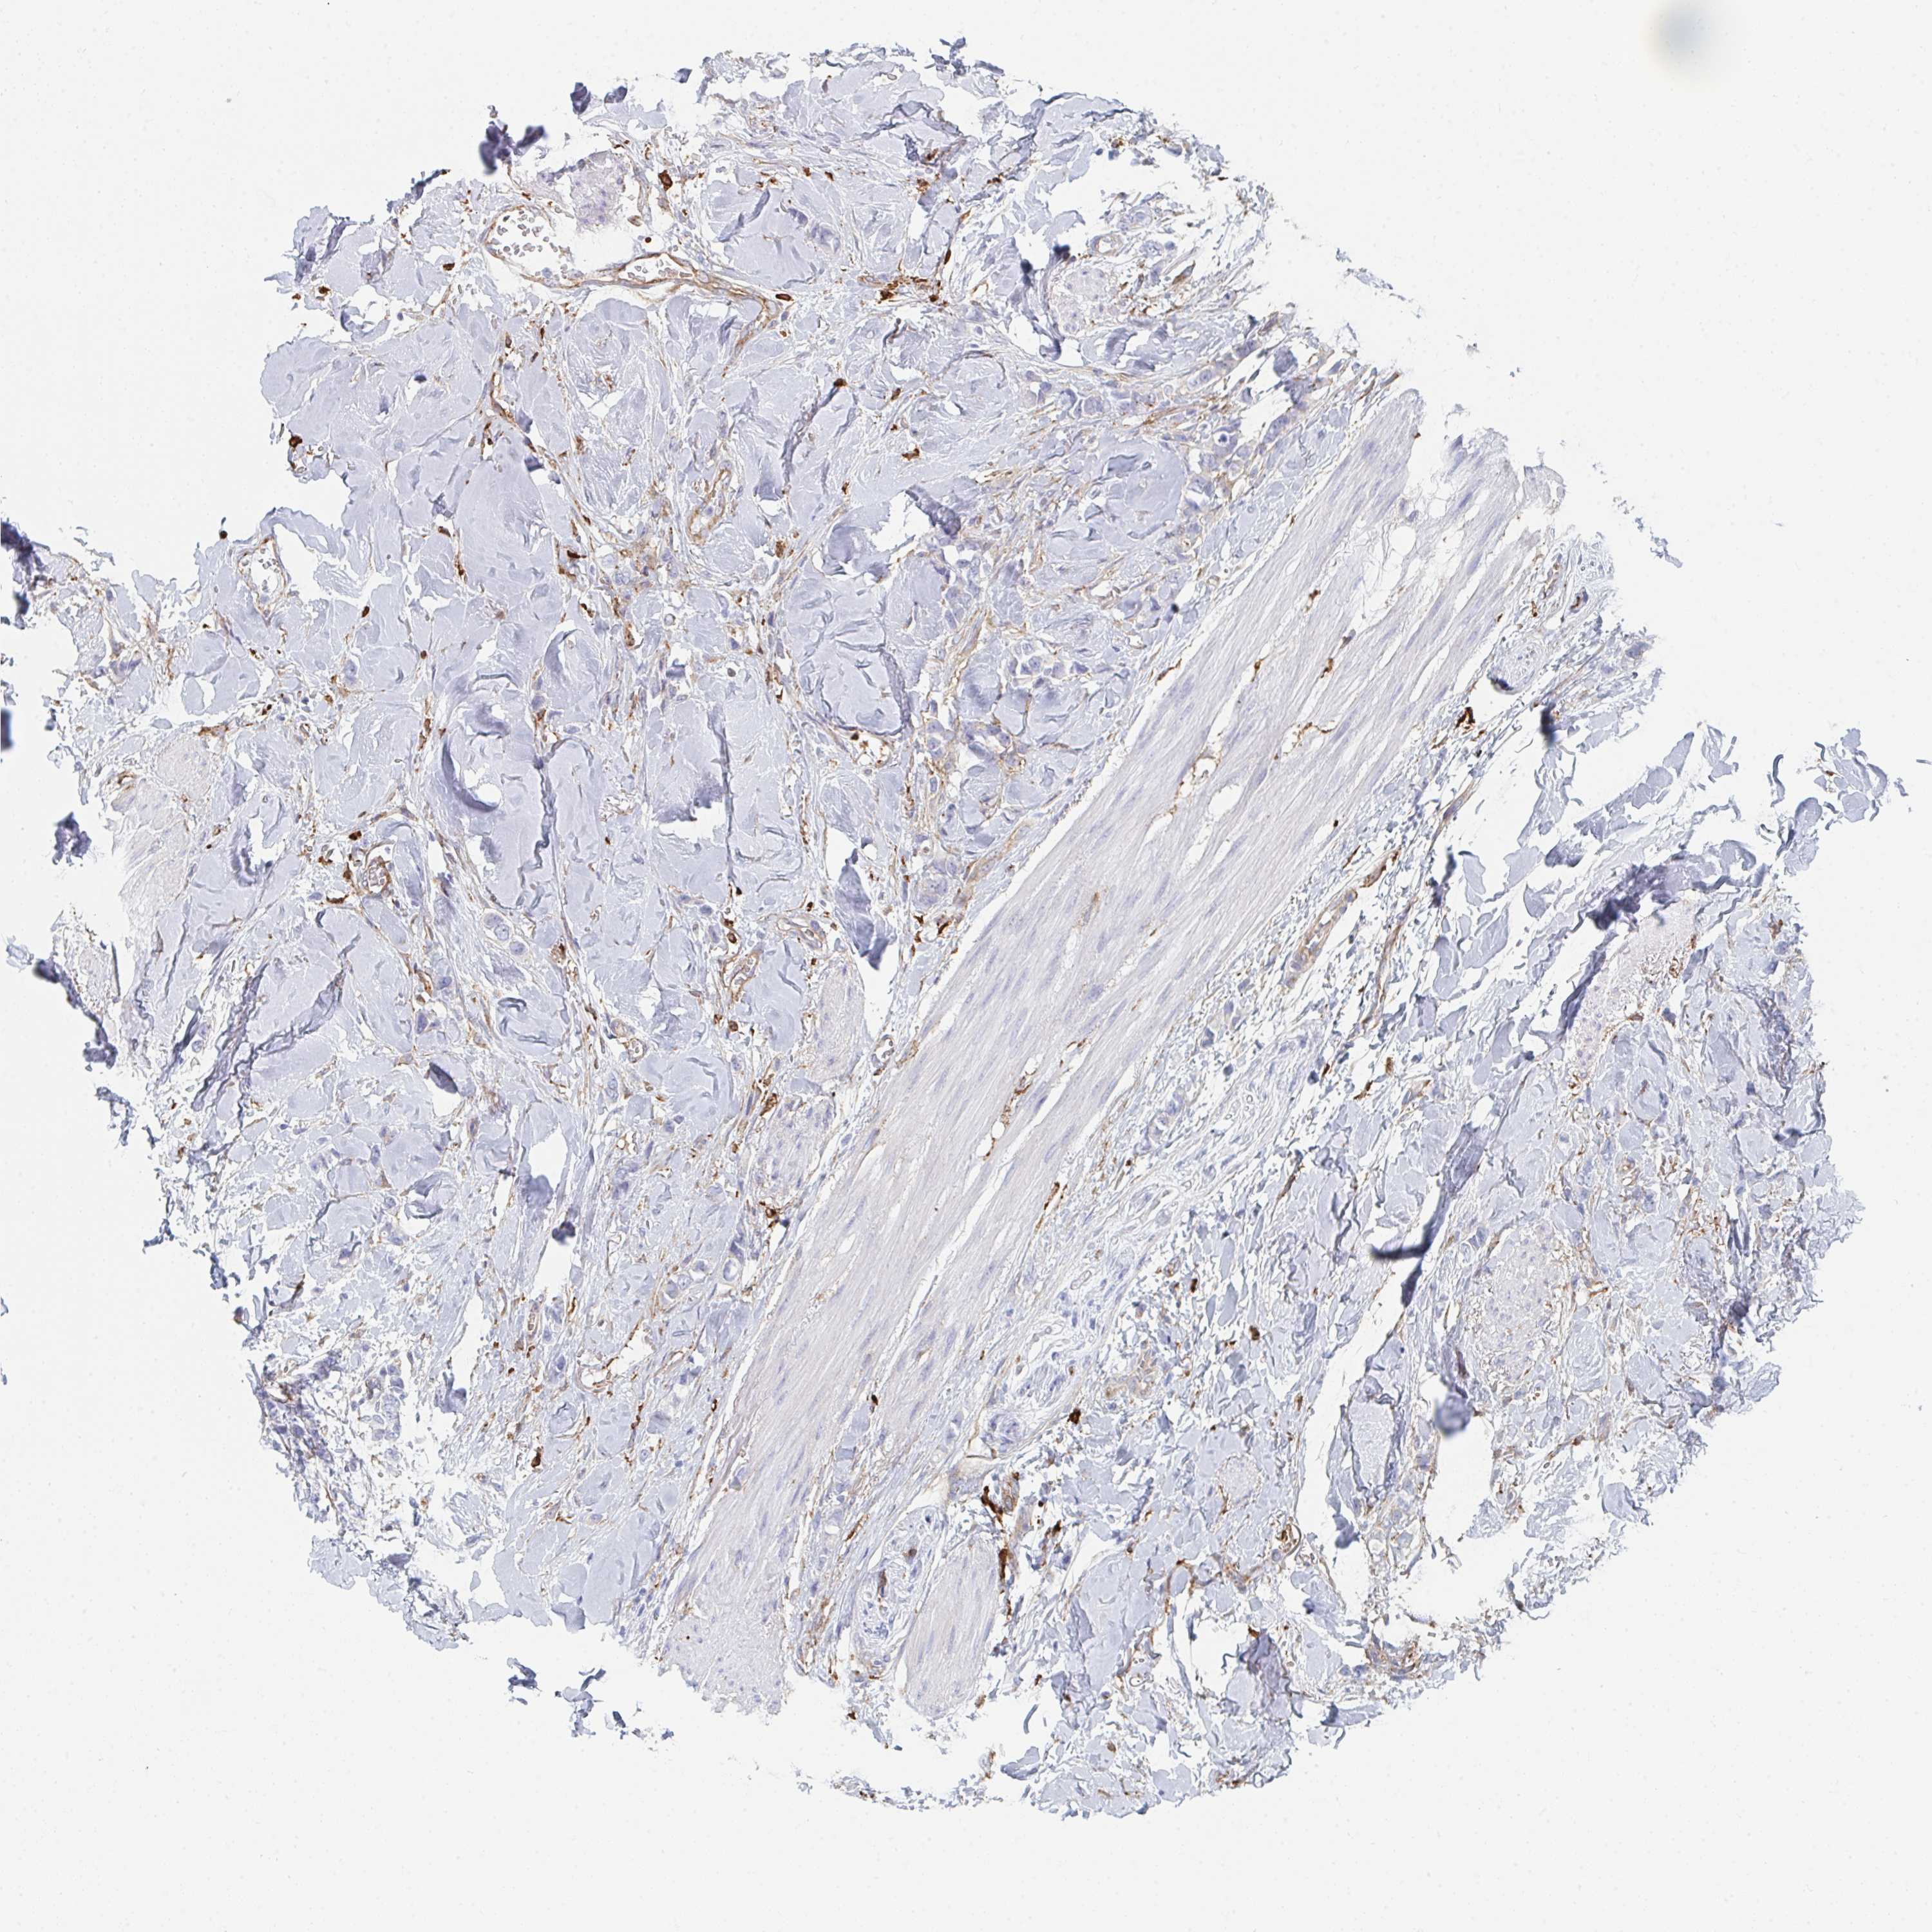

CANCER BREAST CANCER Show tissue menu

BRCA TCGA BRCA VALIDATION PROTEIN EXPRESSION